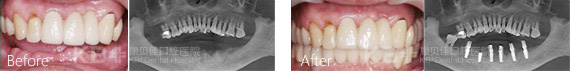

康贝佳经典种植案例

第三次赵大爷下定决心要去种牙,提前预约到了意大利种植牙博士法布里奇奥。针对赵大爷的情况,法布博士给他选择了即刻种植牙技术配合“缺多种少”ALL-ON 4方案,仅需4颗植体恢复半口牙,而且几乎没有疼痛和不适,还省下了不少费用,让赵大爷开心不已。>>>查看赵大爷的种牙费用

赵大爷采用的All-on-4种植牙技术

All-on-4技术对医生的技术和设备有着较高的要求,不是每家医院都可以开展,康贝佳口腔数字化先进设备,针对国人口型对“All-on-4”进行升级和改造,准确种植,安全施术!

All—on—4半口牙缺失更好的种植技术

All—on—4种植技术是欧美先进的口腔种植技术,主要针对于全口无牙或者半口无牙的情况下,利用4颗种植体,于两颗前牙部位的种植体垂直植入牙槽骨内,而两颗中远部位的种植体采取倾斜角度植入牙槽骨内,然后在种植体的基台上安装“拱形连桥”牙冠,这样整个种植牙的受力就呈现出“拱形”的特征,完成口腔种植修复。

节省时间,降低创伤:相对传统的全口、全口种植修复,All—on—4即刻负重技术仅需植入传统种植牙一般的植体,大大降低手术时间和创伤。>>>点击在线医生为您做初步诊断